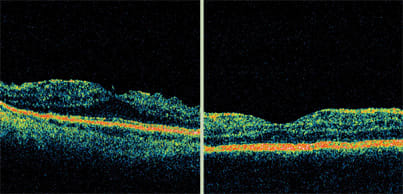

Stratus OCT high-resolution imaging is a reliable way to plan surgery for epiretinal phenomena, such as macular hole, lamellar hole or pseudohole. It clearly shows the full-thickness defect of a macular hole, the anvil-like appearance of a lamellar hole and the blunting of the reflex with a pseudohole. A pseudohole can be due to an epiretinal membrane, which is visible on OCT. Also, a sharp demarcation to the fovea is indicative of a pseudohole.

Stratus OCT images clearly show the full-thickness defect of a macular hole, the anvil-like appearance of a lamellar hole and the blunting of the reflex with a pseudohole. In contrast, on clinical observation and in red-free images, the three conditions look very similar.

A stage 1 macular hole is not a full-thickness defect, as this image shows.

Stratus OCT shows the opening in this stage 2 macular hole.

Stage 3 macular holes are full-thickness defects.

As seen here, stage 4 macular holes are full-thickness and the hyaloid is not attached. In some cases, the hyaloid may be outside the OCT image.

Distinguishing between the three types is difficult with red-free images and clinical observation because they all tend to look as if they are full-thickness defects. Only full-thickness holes require surgery. However, surgery may be performed if an associated epiretinal membrane is present.

The Stratus OCT is useful in staging macular holes. For example, stage 1 holes are not full-thickness and usually resolve on their own. A hole that is not full-thickness but has an opening in it is a stage 2 hole. At this stage, treatment is generally peeling of the hyaloid with gas bubble.

Stage 3 holes are full-thickness. Stage 4 holes are full-thickness without the hyaloid being attached. In both cases, peeling the internal limiting membrane increases the closure rate. In some cases, whether a hole is stage 4 is not evident because the hyaloid can be outside the OCT image.